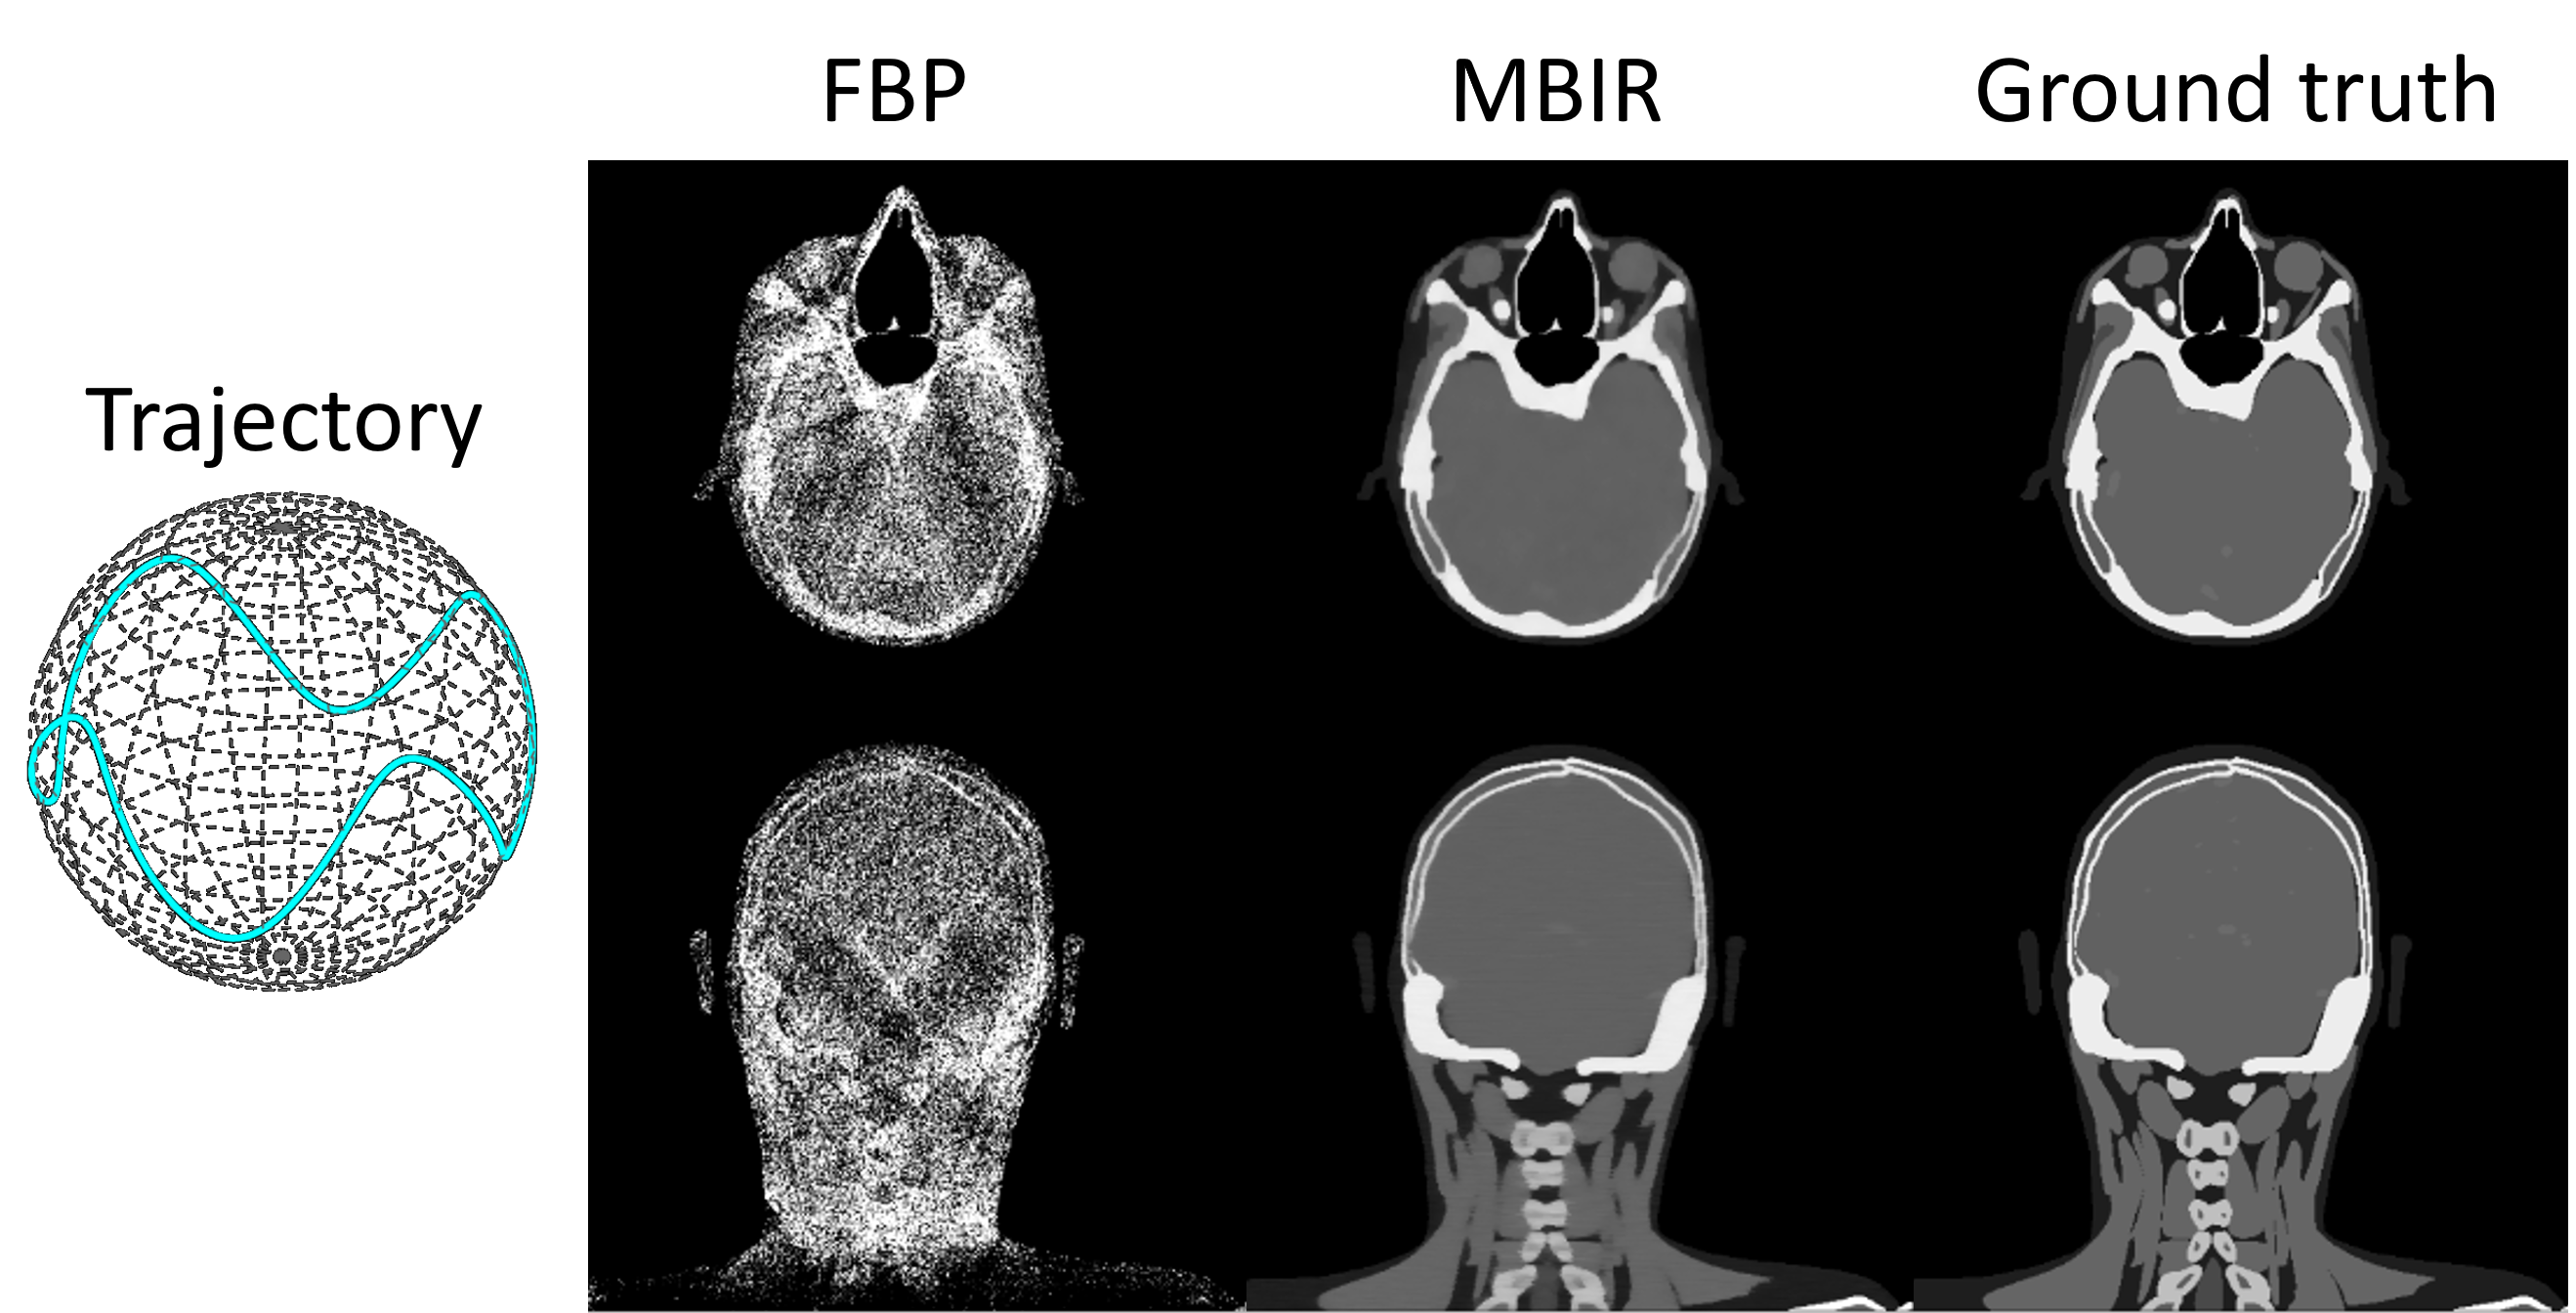

Finally, we validate the effectiveness of auto-differentiation through MBIR. As illustrated in Fig. 7, 200 head[24] cone-beam projections are simulated with a sinusoidal scan trajectory. The objective function of MBIR is formulated as:

The objective function is minimized with 200 iterations of the Adam optimizer where the gradient is computed via auto-differentiation (as shown in the Sec.2.4). Due to the irregular projection sampling pattern, FBP reconstruction exhibits substantial non-uniformity. In contrast, MBIR effectively improves the reconstruction accuracy, as evidenced by a clear depiction of bone and soft tissue boundaries. These results validate the effectiveness of auto-differentiation in conjunction with the CTorch projector.

Figure 7: FBP and MBIR reconstruction of projections simulated with a non-circular scan trajectory.